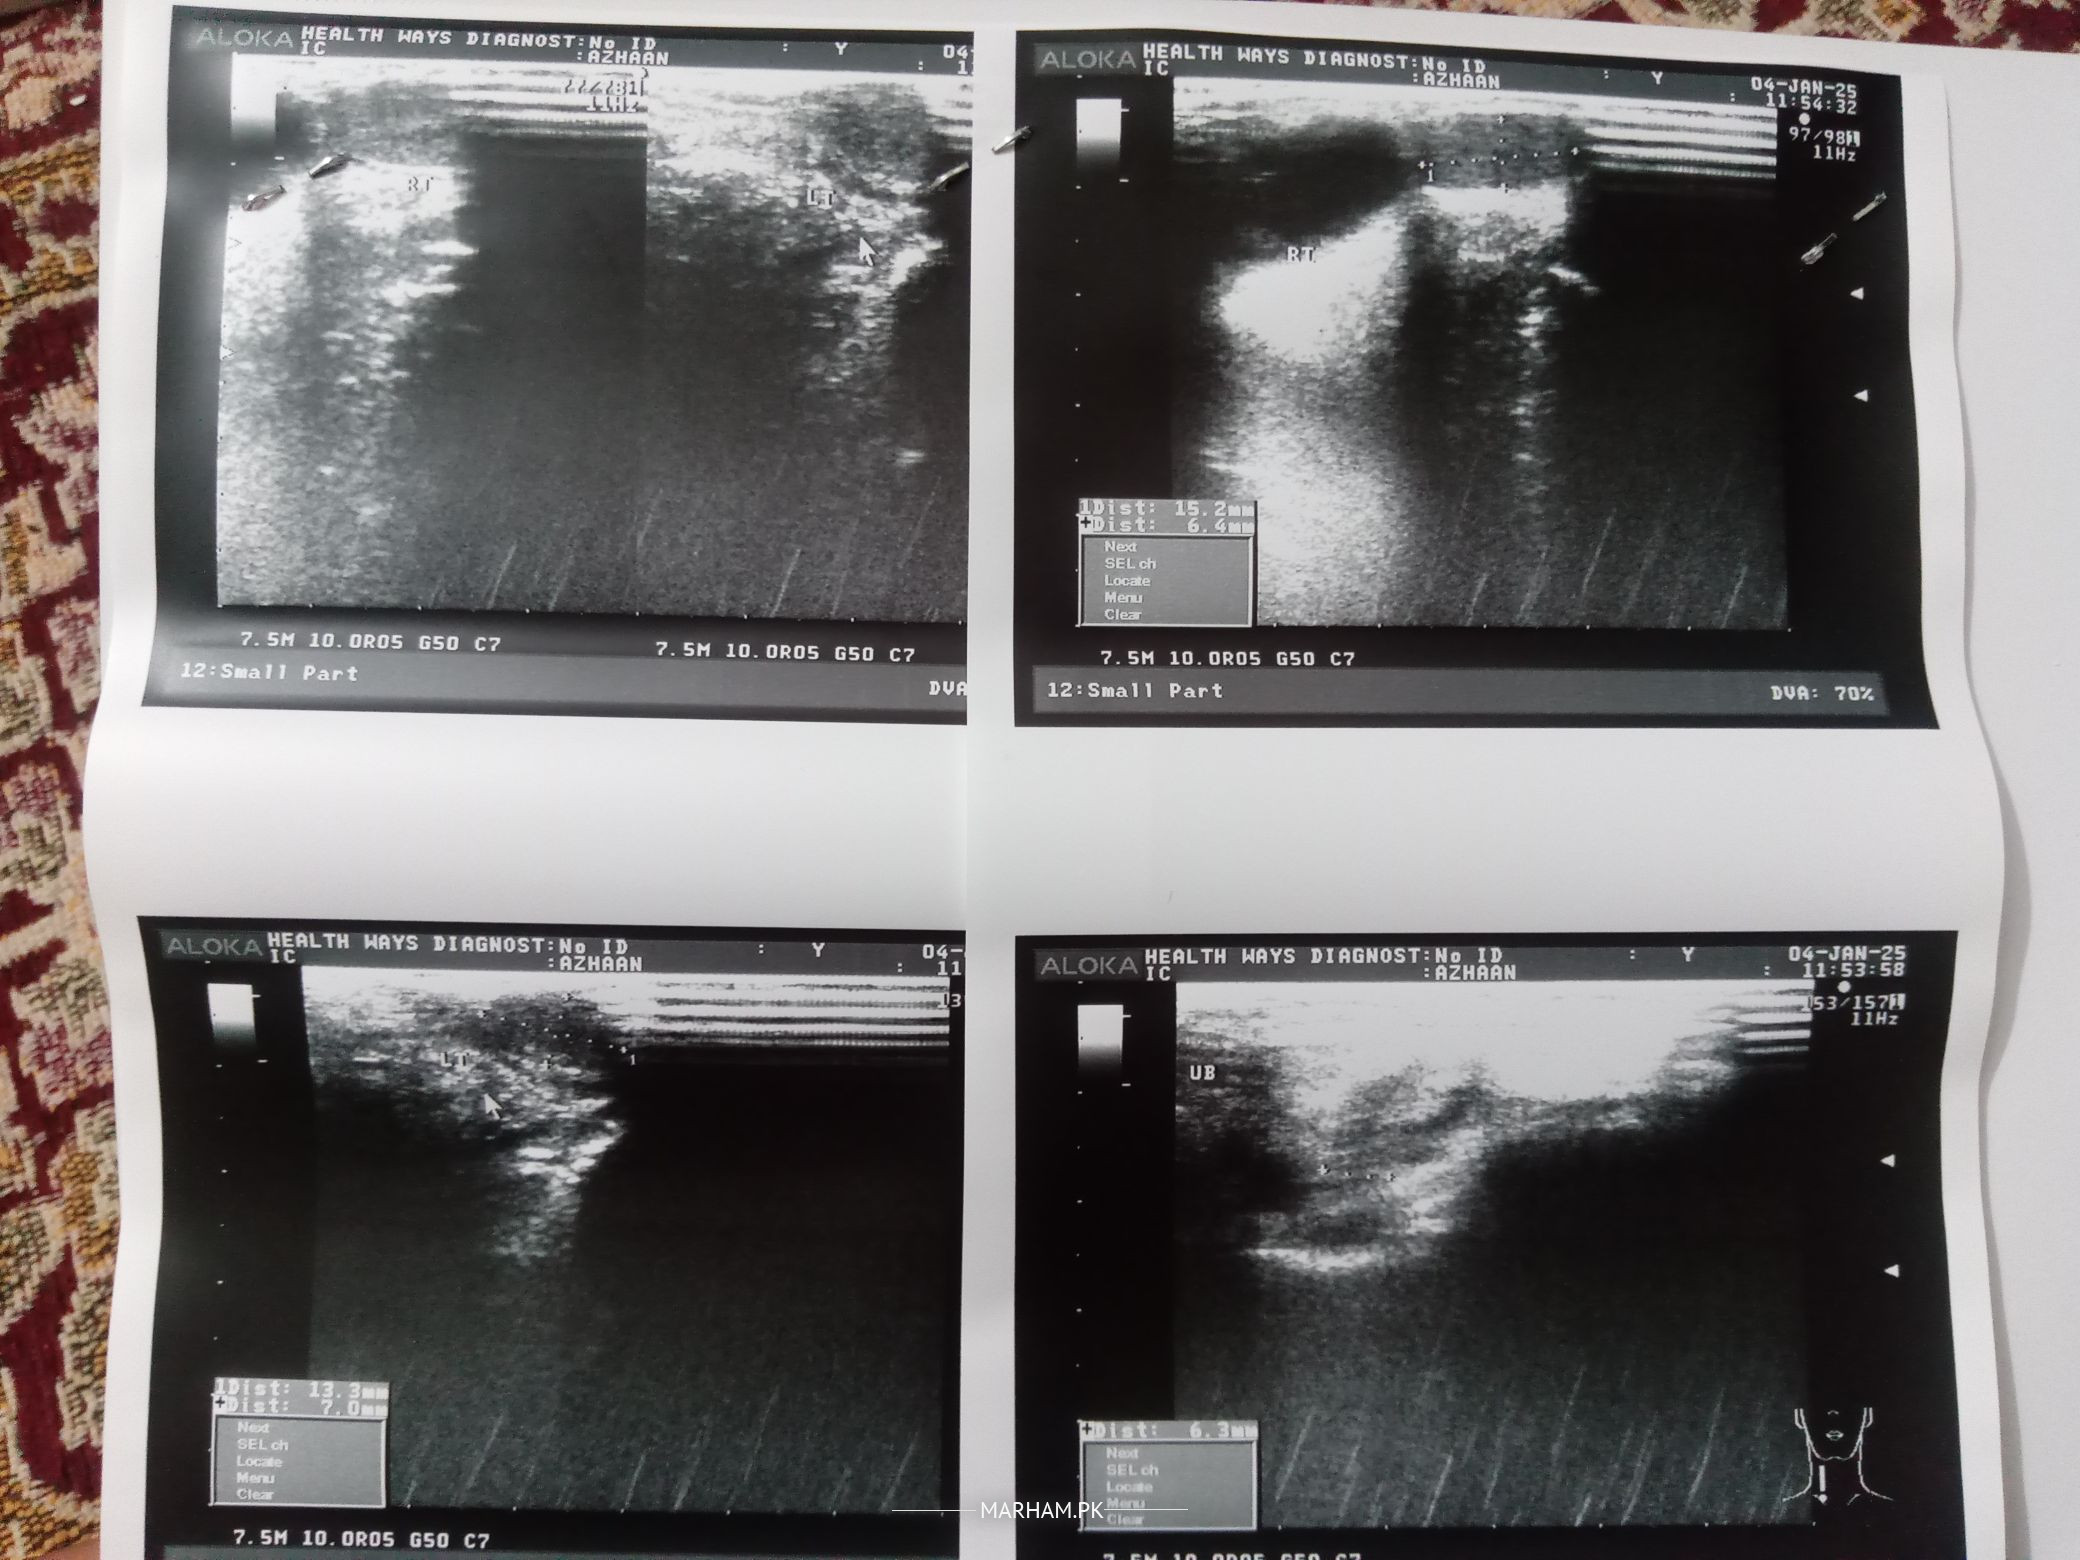

Asalamualykum I want Experienced Opinion. My son is 4 years 2 months old, I'm also attaching his ultra sound reports about inguinal hernia. Is it only Curable With Operation? or I should wait for couple of weeks to check if it heals by its own.

But now from the past 3 days I can see swelling on the right side above scrotum. Today I went to Cantonment Hospital RWP cantt and General surgeon told me after checking the ultrasound reports that we will operate it.